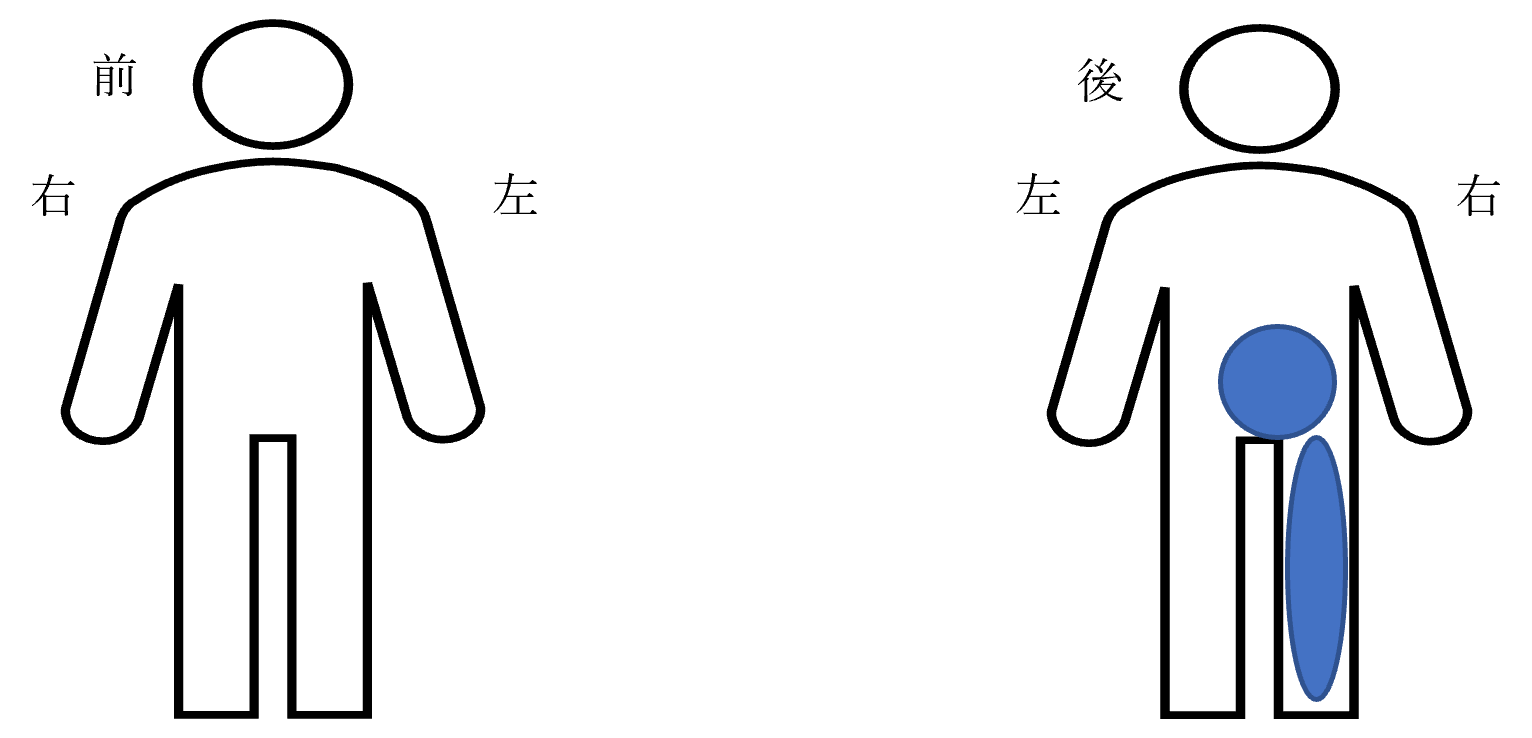

Main areas of pain and numbness: lower back, lower limbs.